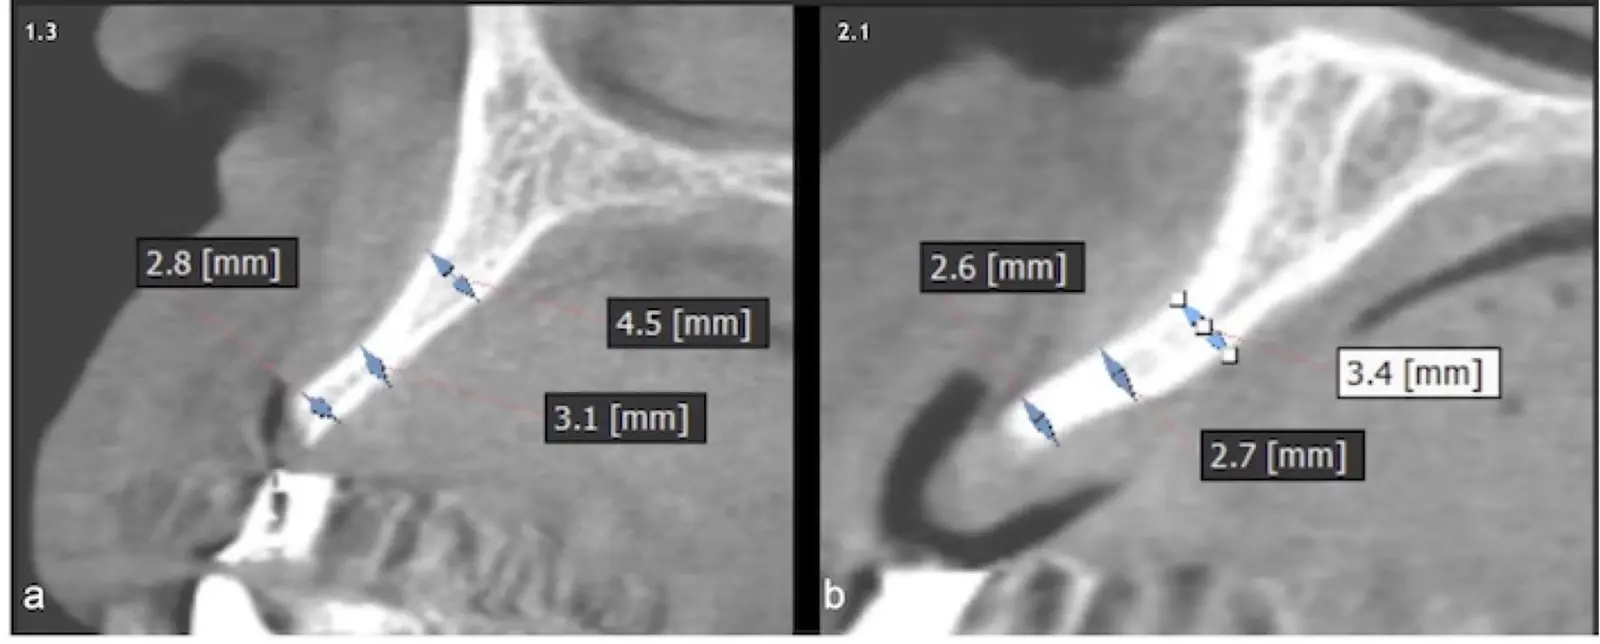

Los casos clínicos que presentamos a continuación muestran claramente las ventajas del piezoeléctrico en diversos procedimientos de terapia ósea regenerativa. En el primer ejemplo, una reconstrucción de reborde con injertos en bloque previo a la planificación de implantes dentales en un caso de edentulismo total superior con una severa reabsorción ósea. En el segundo ejemplo se utilizó esta tecnología para la reconstrucción de lechos para implantes de estructuras óseas con hueso en bloque de origen bovino y posteriormente la colocación de implantes dentales. Los dos casos son parte del capítulo 9 del libro “Cirugía piezoeléctrica: generalidades y aplicaciones clínicas”.